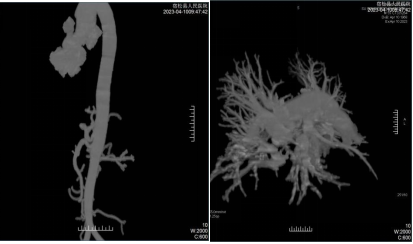

随着我院胸痛中心的建立以及CT检查技术的升级,影像中心CT室成功开展了“胸痛二联一站式CTA”技术,现在只需注射1次造影剂,1次CT扫描即可同时获得肺动脉及主动脉图像,通过工作站VR、MPR、MIP、SSD等后处理技术达到诊断目的。其优点有①一次检查排除肺动脉栓塞、主动脉夹层等疾病,为急诊胸痛患者争取了宝贵的抢救时间,降低了患者的死亡率;② 为临床后续治疗提供了快速、准确的支持;③避免多次检查,降低了患者接受的辐射剂量,降低造影剂使用量,减少了CT检查对患者健康的不利影响,并且减少了患者的检查费用;④此检查技术不仅能了解患者主动脉及肺动脉的疾病,还能观察肺部、气道及腹部的病变。